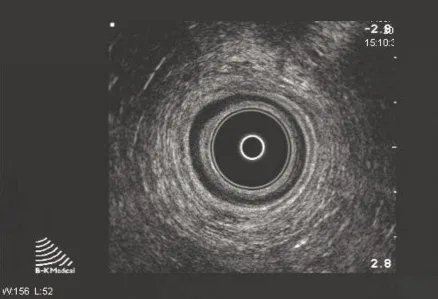

Le canal anal est étudié de haut en bas. Trois niveaux de coupe doivent être systématiquement repérés : coupe supérieure en regard du pubo-rectal (Fig. 1), coupe intermédiaire avec visualisation du SAI et du SAE (Fig. 2), et coupe inférieure avec présence exclusive du SAE.

Figure 2. Coupe au niveau du muscle pubo-rectal

Échoanatomie normale (Figs 1 et 2)

Nous décrirons l’aspect mis en évidence lors d’un examen réalisé avec une sonde rigide. L’interprétation des données anatomiques est complexe. Autour du cône apparaissent des couches concentriques hyperéchogènes et hypoéchogènes (Fig. 2).

La sous muqueuse correspond à la première couche hyperéchogène située directement au contact de la sonde [6].

Le SAI correspond à la première couche hypoéchogène homogène. L’épaisseur du sphincter interne est de 1,5 à 3 mm [6, 7].

L’interprétation du SAE est plus délicate. L’aspect admis par la plupart des auteurs est celui décrit dans l’article princeps de Sultan [8]. Le sphincter anal comporte au total trois couches

et le SAE correspond à la 3e couche

hyperéchogène discrètement hétérogène (située après le SAI). À la partie basse du canal seul le SAE est mis en évidence.On y distingue deux couches séparées par un fin liseré hypo-échogène correspondant à la couche circulaire interne et à la couche longitudinale externe.